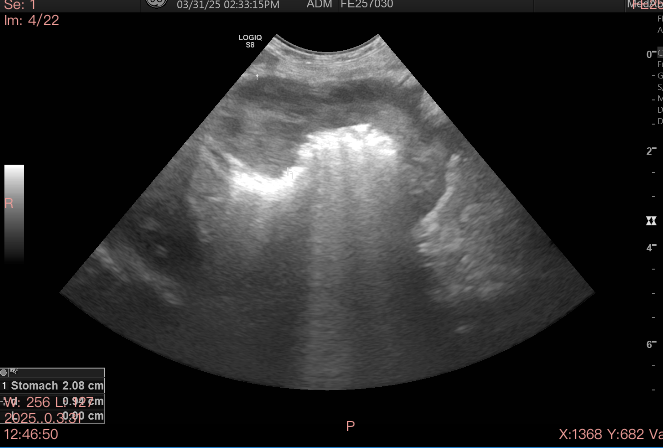

The vet tech took her, then eventually put me in a little room alone. As the hours ticked by, I realized that this might not be okay. This might be something big, something that won’t resolve. I have never been so scared in my life. They did blood work. Not looking good. The ultrasound technician had already gone home for the day. She’d be back in the morning. They wanted to keep her overnight, already the bills and estimates they were handing me were piling up. I asked if I could take her home and bring her back in the morning. The tech asked the doctor, she said it should be okay. I studied her. Is she confident? I took Chookie home and brought her back the next day. A drop off.

A couple days later, Chookie was diagnosed with high grade gastric lymphoma with a mass in the lining of her stomach that had spread to her kidney. Outlook bad.